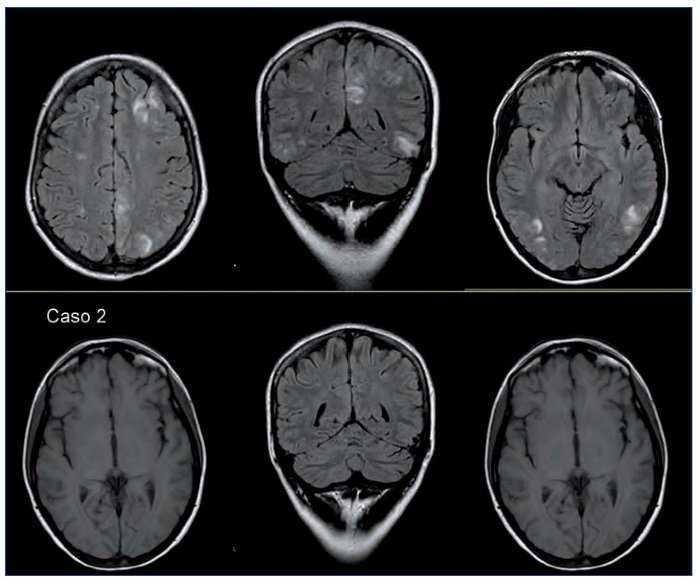

Se realizó una RMNC, que evidenció la presencia de múltiples lesiones, predominantemente de la sustancia blanca subcortical, yuxtacortical y algunas con afectación cortical de localización globalmente simétrica en ambos hemisferios cerebrales y cerebelosas sin restricción de la difusión, compatibles con fenómenos de desmielinización tipo SEPR (figura 2 superior).

Figura 2. Superior: Presencia de múltiples lesiones que afectan a la sustancia blanca subcortical y yuxtacortical y cierta afectación cortical. Se localizan en ambos hemisferios cerebrales, de forma globalmente simétrica, aunque hay áreas de mayor afectación unilateral. Hay lesiones bilaterales y simétricas en ambos hemisferios cerebelosos y a nivel temporobasal, aunque de predominio derecho; también hay afectación parietooccipital bilateral y frontal de predominio derecho, y hay lesiones bilaterales y simétricas en ambas caras mediales de los lóbulos parietales. Se observa una pequeña alteración focal de la señal a nivel profundo localizada en el margen posterior protuberancial a la altura del pedúnculo cerebeloso superior. Inferior: Práctica resolución de las sutiles lesiones hiperintensas córtico-subcorticales bihemisféricas bilaterales supratentoriales.

La RMNC de control a los 2 meses denotó la práctica resolución de las lesiones cerebrales (figura 2 inferior).